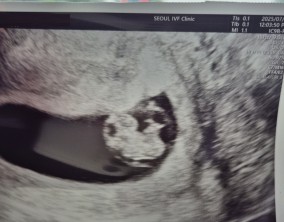

심장소리 이후, 함께 웃게 된 임밍아웃

유정원장님 치료 과정 내내 항상 따뜻하게 진료해 주셔서 감사한 마음이 큽니다. 덕분에 불안한 순간에도 마음을 다잡고 치료를 이어갈 수 있었습니다.